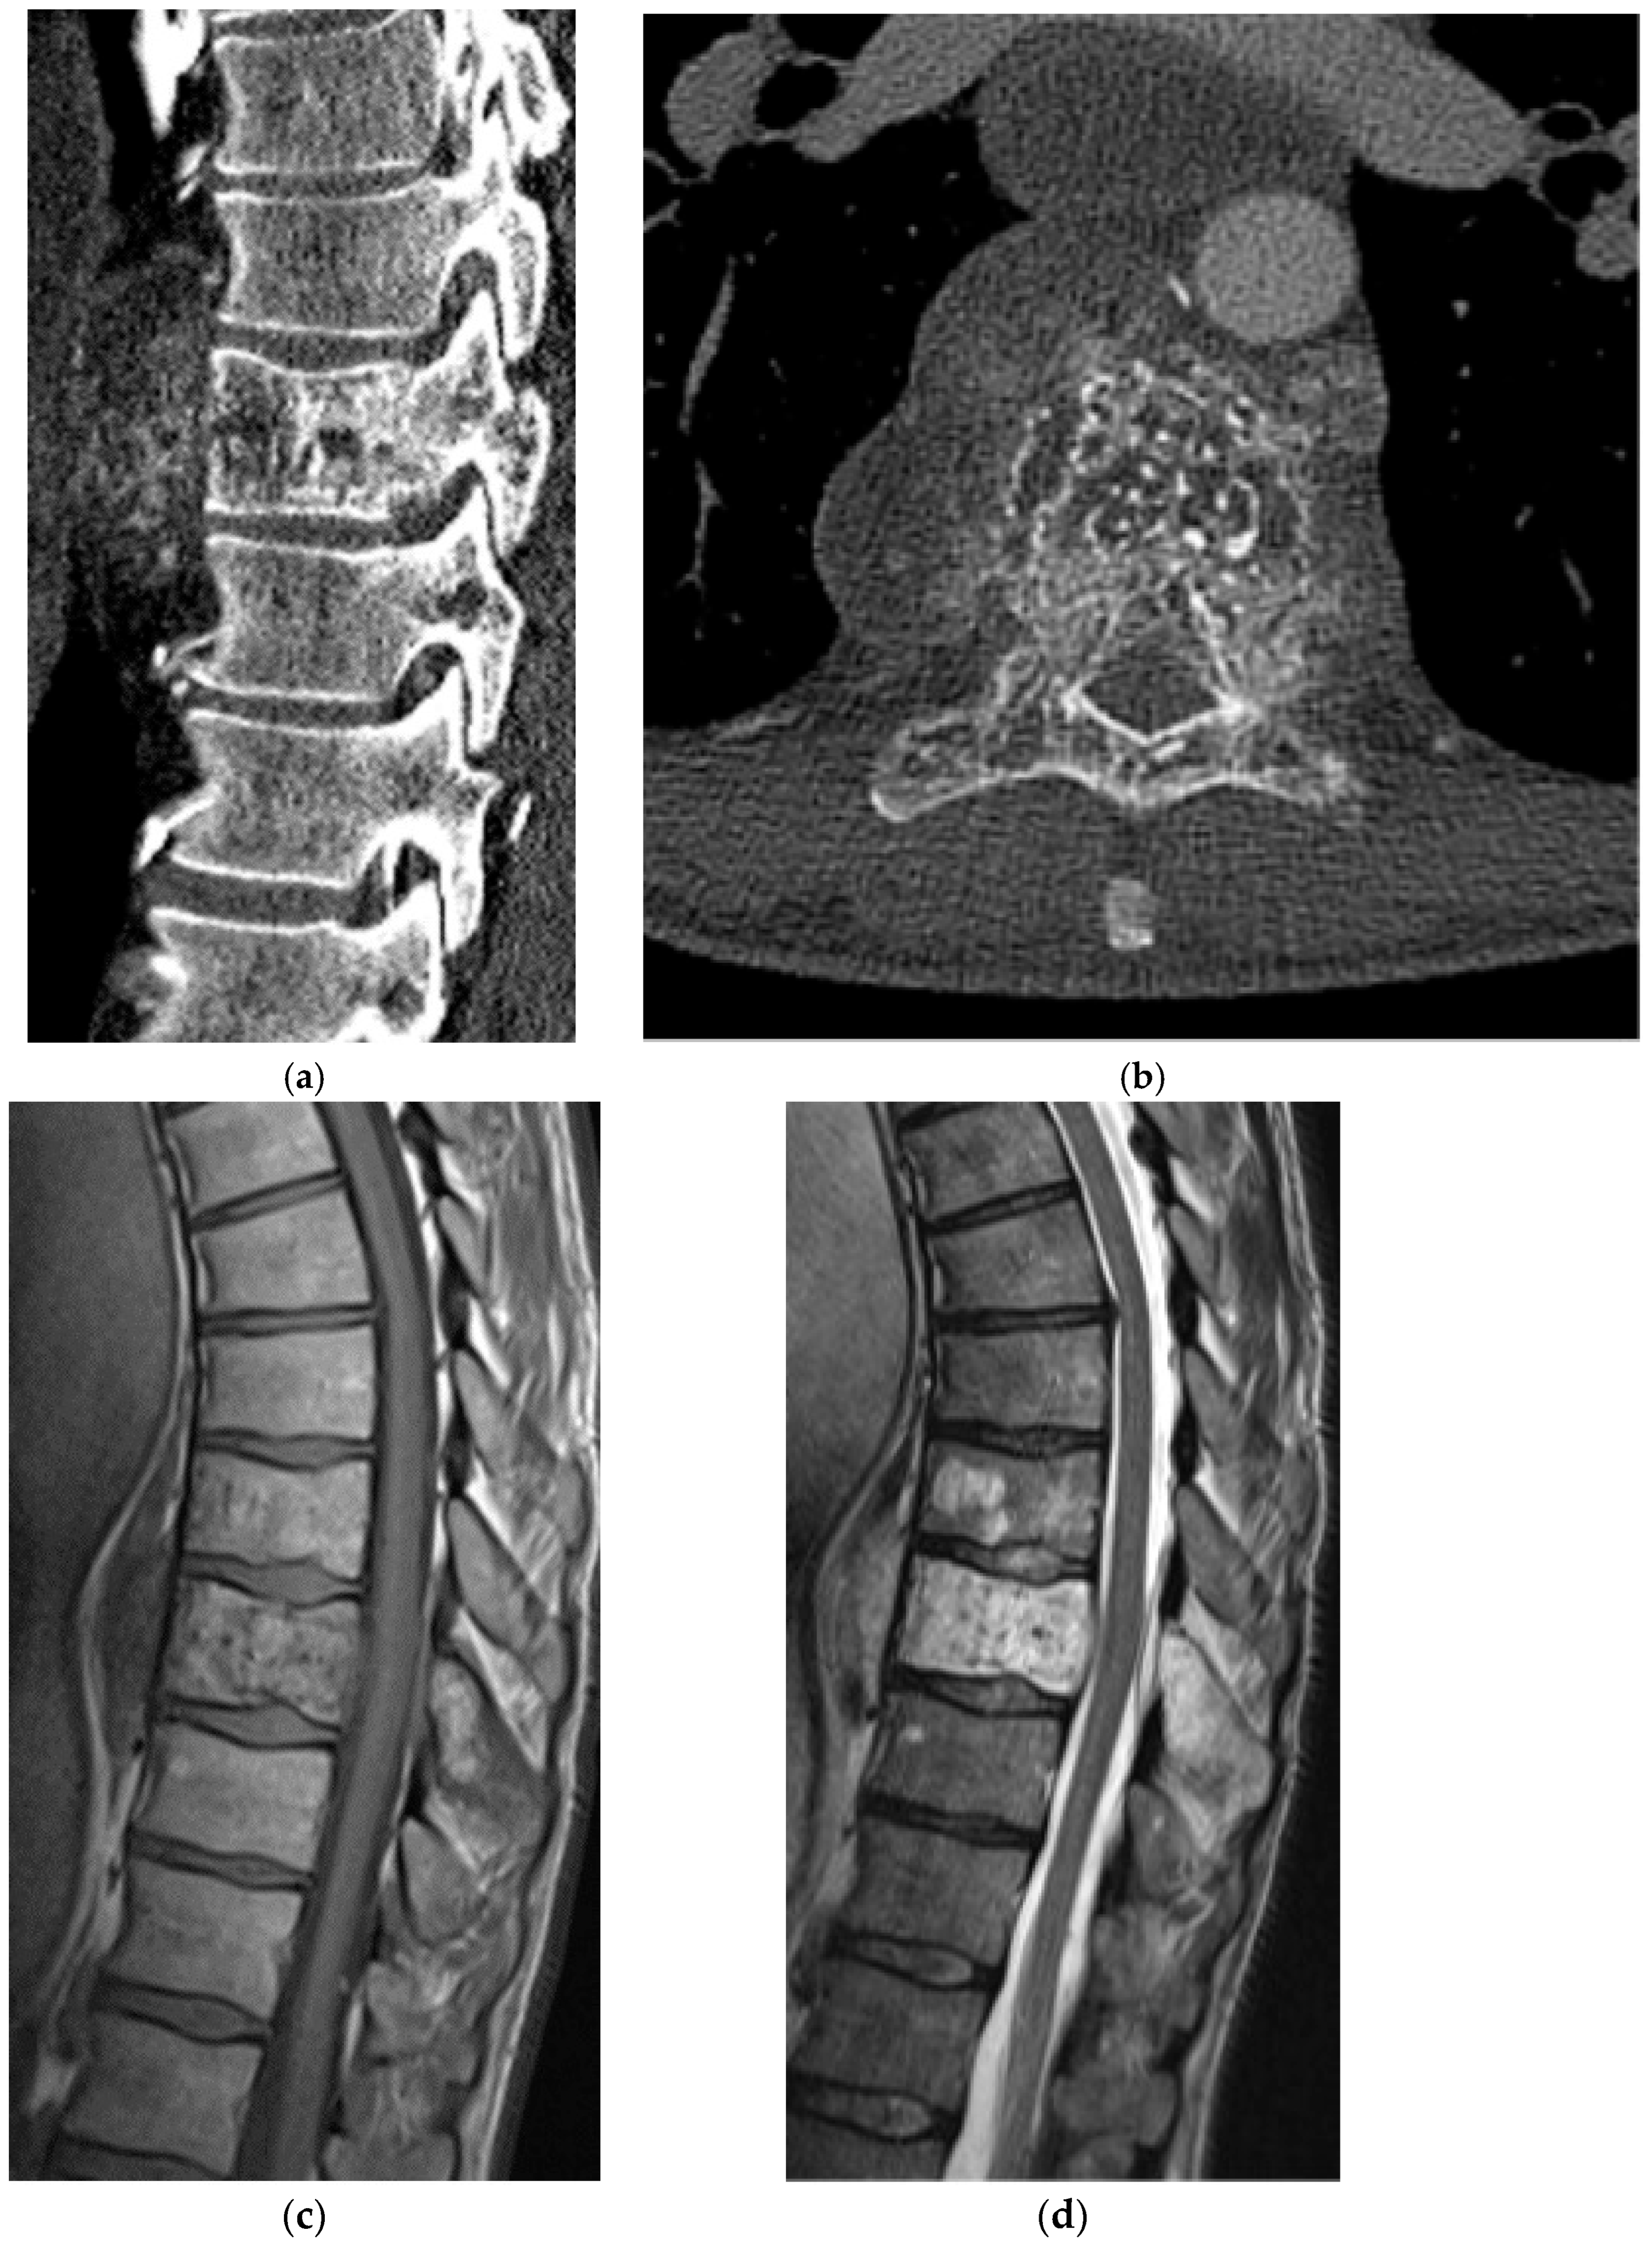

Paget’s Disease